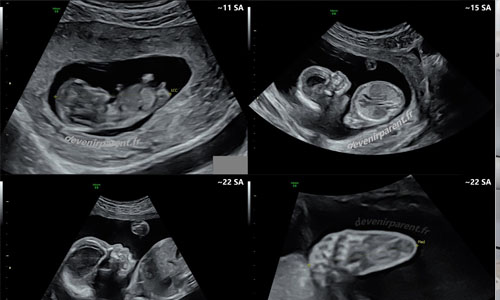

Le Centre d’Imagerie Médicale MATUSILA (C.K.R) propose un service de radiologie et d’imagerie médicale sur l’ensemble des activités de radiologie en RDC: radiologie numérisée générale, radiologie numérisée spécialisée, radiologie interventionnelle, scanner, IRM, échographie, écho-doppler etc..

Notre équipe de radiologues spécialisés vous accueille pour l’ensemble de vos examens d’imagerie : mammographie, échographie et Doppler, système EOS, radiographie, IRM, panoramique dentaire, imagerie pédiatrique ainsi que de nombreux autres examens moins fréquents.